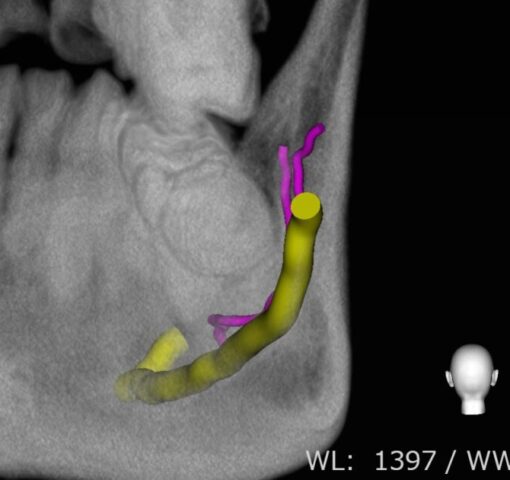

黄色が神経(下歯槽管)、ピンクが神経(下歯槽管)から分岐です。

神経の位置や走行を立体的に把握することで

抜歯方法の選択

歯根分割の位置

削除量の最小化

神経への接触回避

を事前に計画できます。